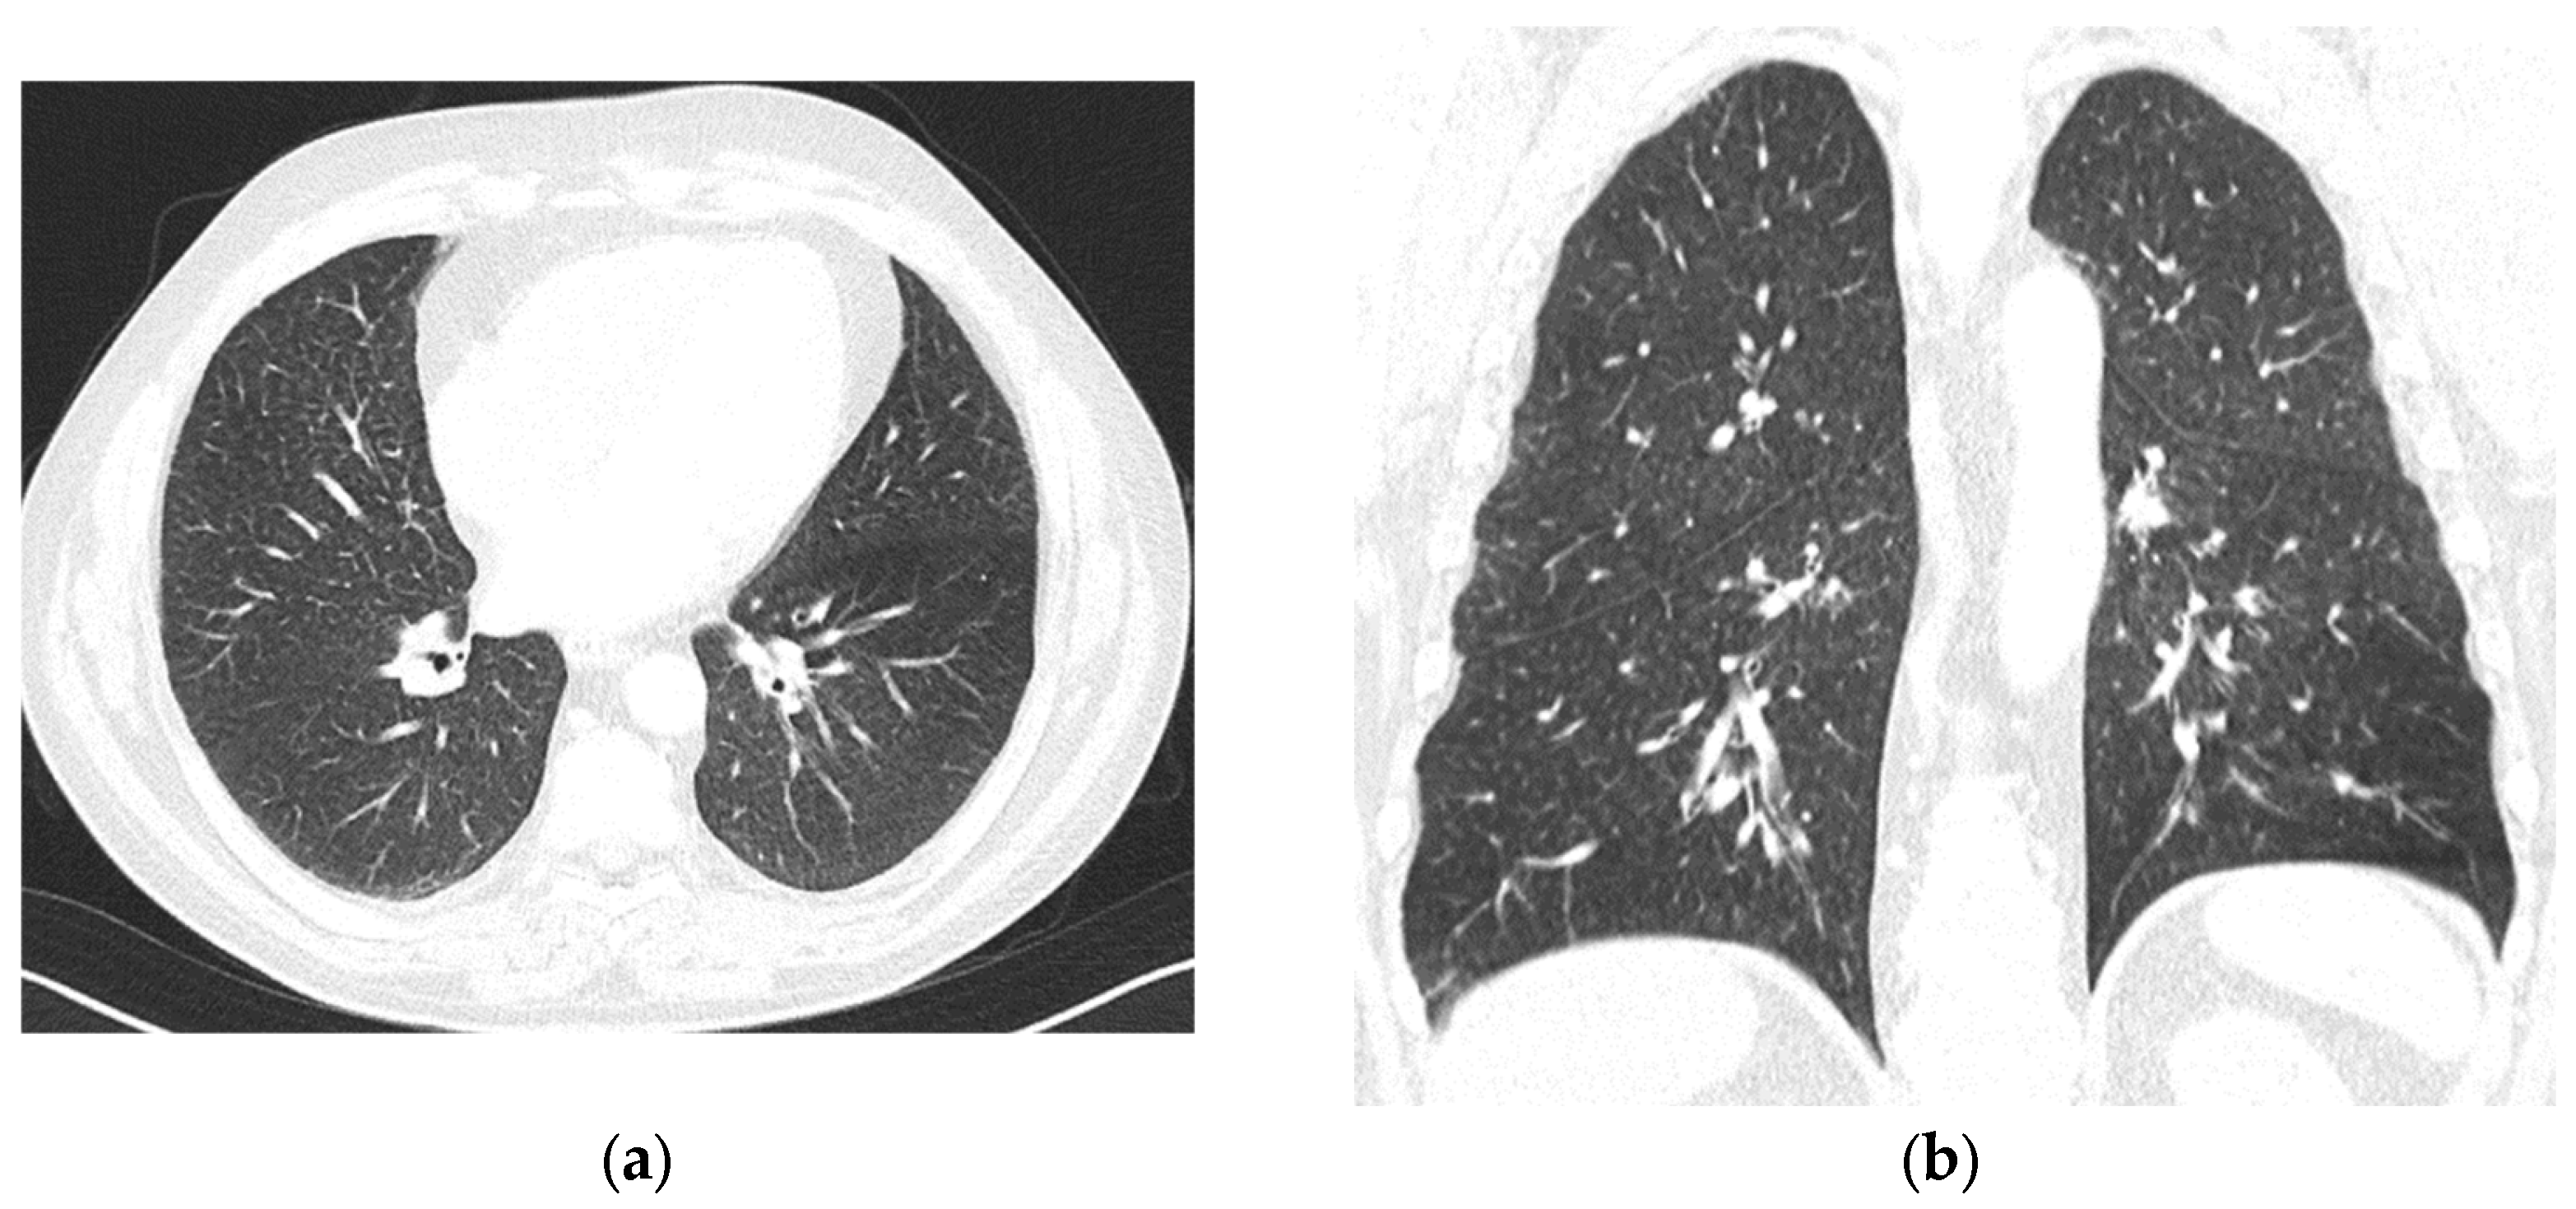

Decitabine was withdrawn, and we assumed an adverse reaction to both medications. We decided to proceed directly to allo-HSCT. Meanwhile, the patient received intermittent pulses of prednisolone to manage persistent bone pain in the lower limbs, which had been present since the initial diagnosis. Despite Hb levels being > 11 g/dL, he started feeling tiredness two months after decitabine withdrawal. The patient was referred to the pulmonology department. A thoracic CT scan revealed symmetric, diffuse lung involvement with nonspecific interstitial findings and centrilobular changes suggestive of small airway involvement (Figure 2). A potential toxic hypersensitivity reaction with associated bronchiolitis was considered. Pulmonary function tests showed moderate bronchiolar and bronchial obstruction without hyperinflation, with a slight improvement (12%/260 mL increase in FEV1) following bronchodilator administration. Alveolar–capillary diffusion capacity (DLCO) was normal, and partial respiratory insufficiency was noted with a PaO2 of 71.1 mmHg. Treatment with inhaled corticosteroids, a long-acting muscarinic antagonist (LAMA), and a long-acting beta-agonist (LABA) was initiated and maintained. Respiratory bronchiolitis-associated interstitial lung disease (RB-ILD) and chronic obstructive pulmonary disease (COPD) were considered. Six months later, a follow-up thoracic CT scan showed stable diffuse interstitial and centrilobular changes.

Figure 2. (a,b) Thoracic CT scan, after decitabine withdrawal and in the presence of respiratory symptoms, showing symmetric, diffuse lung involvement with nonspecific alterations and centrilobular alteration suggestive of small respiratory tract involvement.